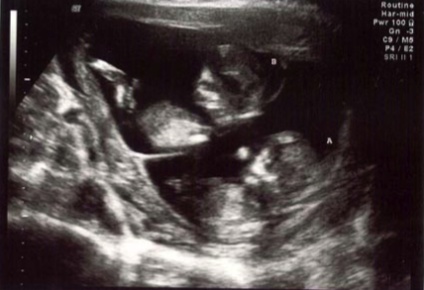

Tuesday, February 17 – Back to the perinatal specialist today for a big anatomy ultrasound. The exam lasted over an hour and a half. During it we got to see each baby’s hands, feet, legs, spine, skull, heart, kidneys and other organs – and we found out we’re having two girls!! When I told Dan he was going to be outnumbered, he said that was OK, he likes girls.